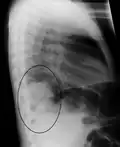

AP CXR showing left lower lobe pneumonia associated with a small left sided pleural effusion -

Right lower lobe pneumonia as seen on a lateral CXR